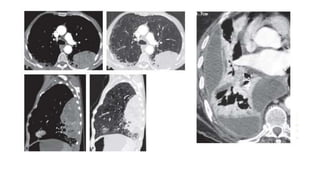

X ray

• Bilateral area of multifocal,

discontinuous pleural thickening.

• Sparing of apex and

costophrenic angle

• Characteristic serpentine

marginal calcification (so-called

holly leaf pattern of calcification)

in peripherally calcified plaques

imaged en face(PA)

CT

• Multifocal discontinuous

bilateral pleural nodules; most

profuse along paravertebral

pleural surfaces and

posterolateral chest wall.

X ray • Bilateralarea of multifocal, discontinuous pleural thickening. • Sparing of apex and costophrenic angle • Characteristic serpentine marginal calcification (so-called holly leaf pattern of calcification) in peripherally calcified plaques imaged en face(PA)

• 23.

CT • Multifocal discontinuous bilateralpleural nodules; most profuse along paravertebral pleural surfaces and posterolateral chest wall.